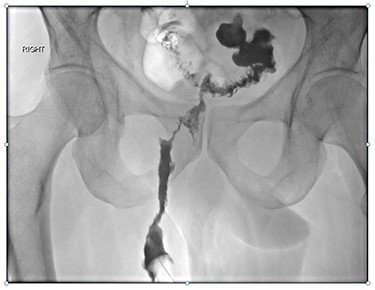

Magnetic resonance imaging (MRI) identified a fistulous tract extending from the sigmoid colon, around the anterior aspect of the anal canal, with small collections in the ischiorectal and ischioanal fat. CT fistulogram showed a long fistulous tract extending from the right peri-anal region to a sigmoid diverticulum above the recto-sigmoid junction (Figs 1 and 2). The patient underwent a second EUA at which a large tract was identified at 9 o’clock, running parallel to the anus and rectum, with no apparent connection to the anus but draining enteric content. The superior extent of the tract was not felt. Colonoscopy showed a benign-appearing, intrinsic moderate sigmoid stenosis measuring 2 cm in length, which was traversed with difficulty.

(A) CT fistulogram showing a long fistulous tract extending from the right peri-anal region, superiorly in the ischiorectal fossa, traversing the inferior aspect of the levator ani and extending around the right of the anal canal and rectum; (B) superiorly, it extended into a thick-walled inflamed segment of sigmoid colon with numerous diverticulae; contrast can be seen entering the sigmoid loop.